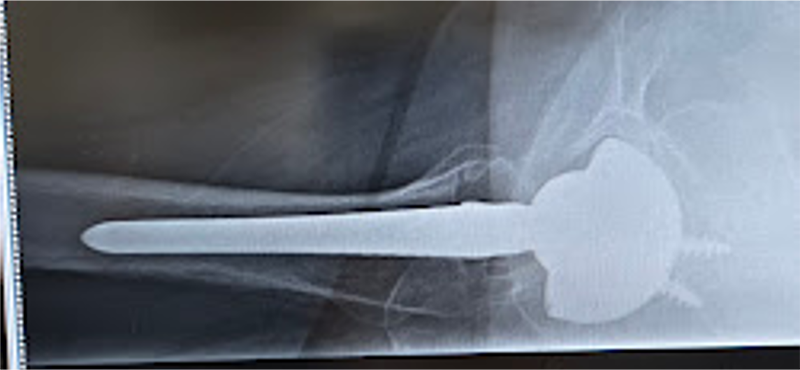

〈手術後のレントゲン〉(側面)